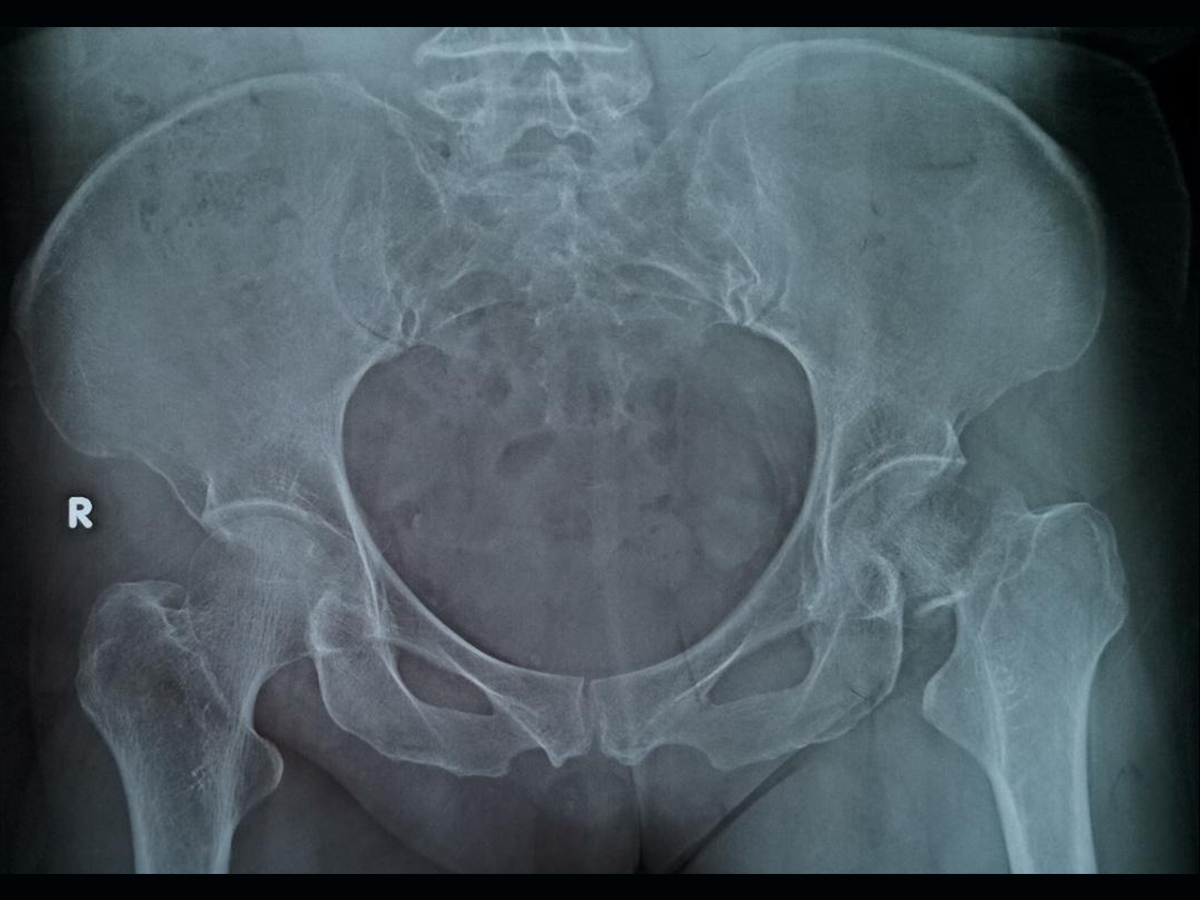

冬天天冷路滑,稍有不慎就会摔倒,患者张奶奶在出门遛弯的时候滑倒,受伤后出现了左髋部疼痛,行走困难。随即由家人送至急诊室,通过查体发现存在左下肢较右侧明显向外旋转,左侧足尖大约呈45°转向外侧的表现,即股骨头骨折的典型表现。行X线检查,证实了股骨头骨折的诊断,且骨折线正好位于左侧股骨头下,骨折端明显移位,患者最终确诊为左股骨颈骨折(头下型)。

【疾病类型】左股骨颈骨折(头下型)